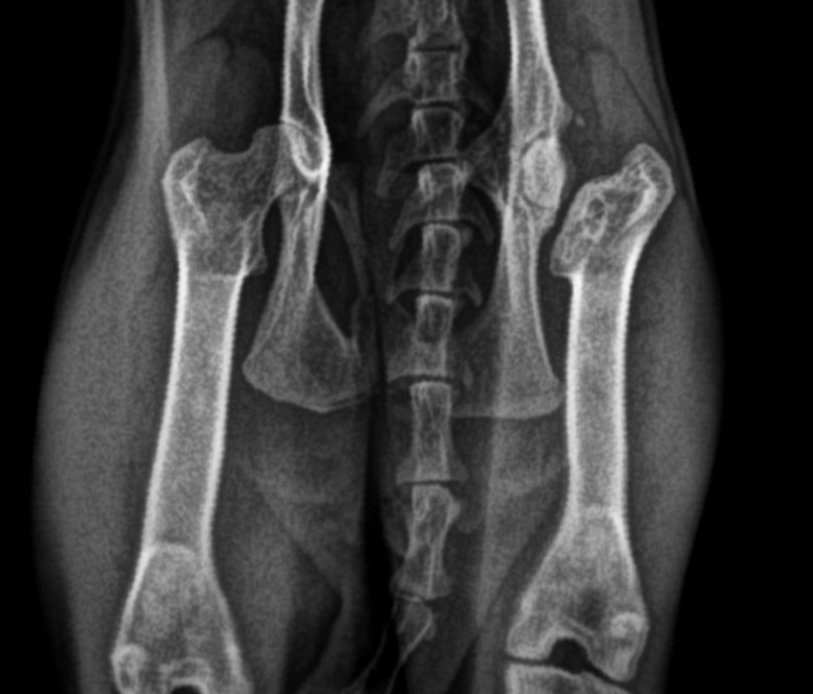

A 2-year-old male rescue domestic shorthaired cat was presented to the clinic with a history of hindlimb lameness and pain following an unknown traumatic event.

The cat was recently rescued from the street and had been non–weight-bearing on the left hindlimb for several days before presentation.

• Left hindlimb showed:

• Marked pain and crepitus on manipulation of the hip joint.

• Limb shortening and external rotation of the stifle.

• Non–weight-bearing lameness.